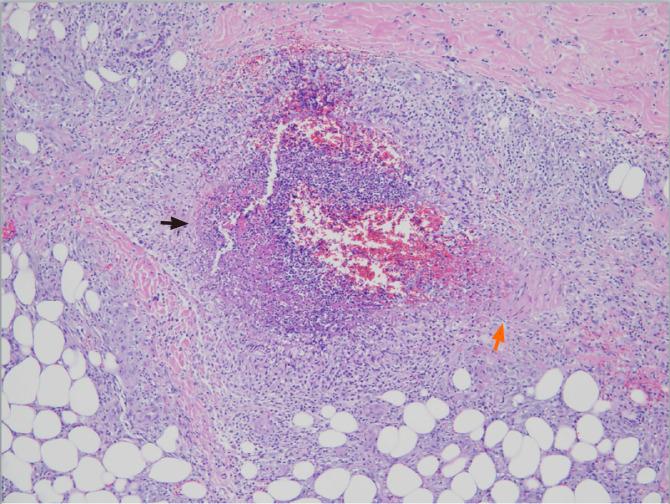

人类肝炎病毒相关的皮肤和系统性血管炎。

Human hepatitis viruses-associated cutaneous and systemic vasculitis.

人类肝炎病毒(HHV)包括甲型肝炎病毒、乙型肝炎病毒(HBV)、丙型肝炎病毒(HCV)、丁型肝炎病毒和戊型肝炎病毒,可在共同的人类宿主中引起肝脏炎症。通常,急性HHV入侵后,免疫系统会迅速清除HHV。甲型肝炎病毒和戊型肝炎病毒感染相关的发病率在入侵后不久的急性期出现。然而,病毒感染过程可能会持续很长时间,尤其是在HBV和HCV感染中,会导致慢性肝炎,并进一步发展为肝硬化和肝癌。HHV感染会引发其他器官的并发症,急性和慢性肝炎都与肝脏以外的临床表现有关。血管受累伴皮肤和系统性血管炎是一种众所周知的肝外表现;此外,越来越多的证据表明病毒病原体与血管炎之间可能存在因果关系。除丁型肝炎病毒外,其他HHV通过不同机制参与了皮肤和系统性血管炎的发病机制,包括病毒直接侵袭血管内皮细胞、免疫复合物介导的血管壁损伤以及自身反应性B细胞受刺激和调节性T细胞受损引起的自身免疫反应。冷球蛋白血症性血管炎和结节性多动脉炎因其与慢性HHV感染的关联而被认可。虽然尚未建立HHV相关血管炎的治疗指南,但除使用皮质类固醇外,对于HBV和HCV相关的系统性血管炎应启动抗病毒治疗。对于有严重危及生命的血管炎表现的患者,可考虑进行血浆置换和/或联合环磷酰胺和皮质类固醇治疗。